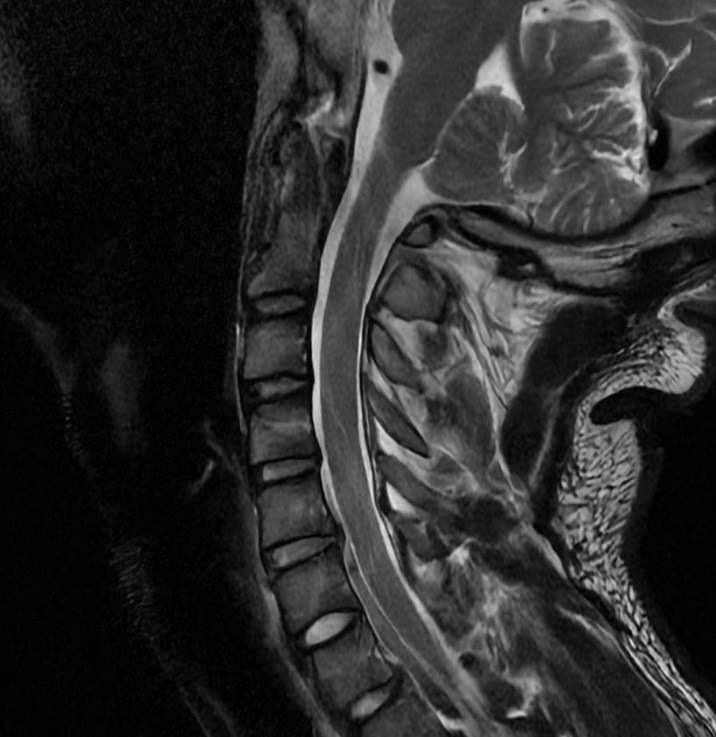

In February 2023, I suffered a severe neck injury whilst practicing CrossFit that completely changed my life. I was 22, healthy, and active, but the accident set off a medical decline that has continued for almost 3 years and is ongoing. Despite consulting multiple neurologists and neurosurgeons and following every treatment I was offered, I was repeatedly misdiagnosed, reassured, or told to “wait” while my condition worsened. I have been neglected by the medical system for years now. By the time more serious possibilities were finally considered, significant and avoidable damage had already taken place and is still taking place every day that passes.

What began as a single herniated disc has progressed into widespread cervical degeneration, loss of cervical lordosis, osteophytes, and even brain scarring from recurrent TIAs linked to vascular involvement in my neck. I am now 25 and disabled. I live in constant, severe neck pain and can barely move my head or stay upright for more than a few minutes without dizziness, disorientation, and extreme discomfort. I, unfortunately, already have irreversible symptoms like nerve damage all over my left limbs and severe difficulty with fine motor function.

My everyday symptoms include difficulty breathing and swallowing, intense dizziness and stabbing pain with head movement, double vision, metallic taste, severe cognitive problems, loss of sensation in my limbs, hearing loss in one ear, major loss of dexterity, weakness and heaviness in my arms and legs, blurred vision, painful spasms, electric shock sensations when looking up, insomnia, and persistent visible heart palpitations. Basic tasks like walking, eating, thinking, and simply holding my head up have become a struggle. My condition is progressively worsening, and it is very likely that more cervical segments are already damaged.